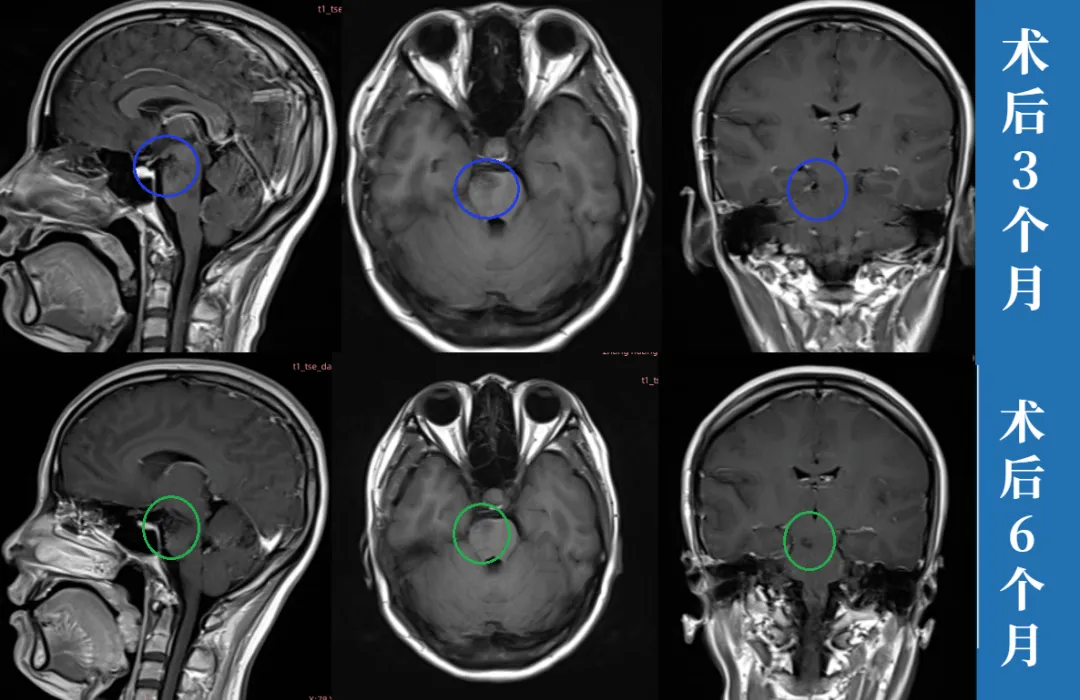

最终,萱萱决定找巴教授为其主刀切除这个脑袋里的“麻烦”。在巴教授中国行示范手术期间为萱萱顺利全切近20mm的脑干深处病变,术后无瘫痪、无视神经损伤、无呼吸抑制和昏迷风险,术后萱萱的恢复状况也很好。

如今,早已恢复正常工作和生活的萱萱,恢复状态良好,并且在今年年初迎来自己宝宝。